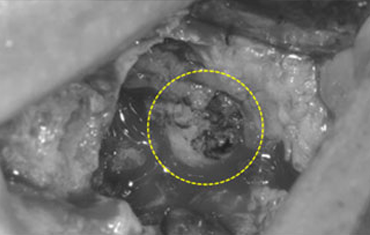

뼈의 소실량이 많은 경우

매복된 제2 대구치

매복된 사랑니

견고한 금속 차폐막 적용